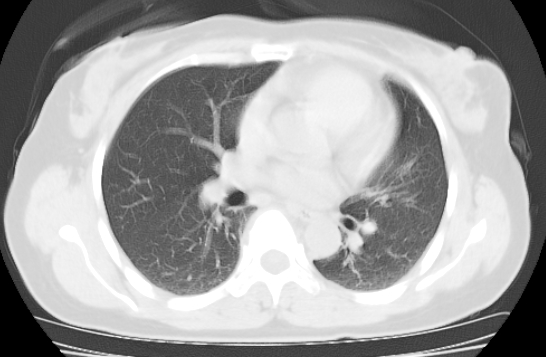

标题: CT25227:背部疼痛伴双侧胸壁痛2月,食欲差。 [打印本页]

标题: CT25227:背部疼痛伴双侧胸壁痛2月,食欲差。

肺结核并胸椎结核?请各位高手指教。

用椎体的条件来扫胸椎呀!考虑1左侧胸膜小结节形成2椎体结核并冷脓肿形成

左肺结核灶,胸椎结核并冷脓肿。

左肺结核灶,胸椎结核并冷脓肿